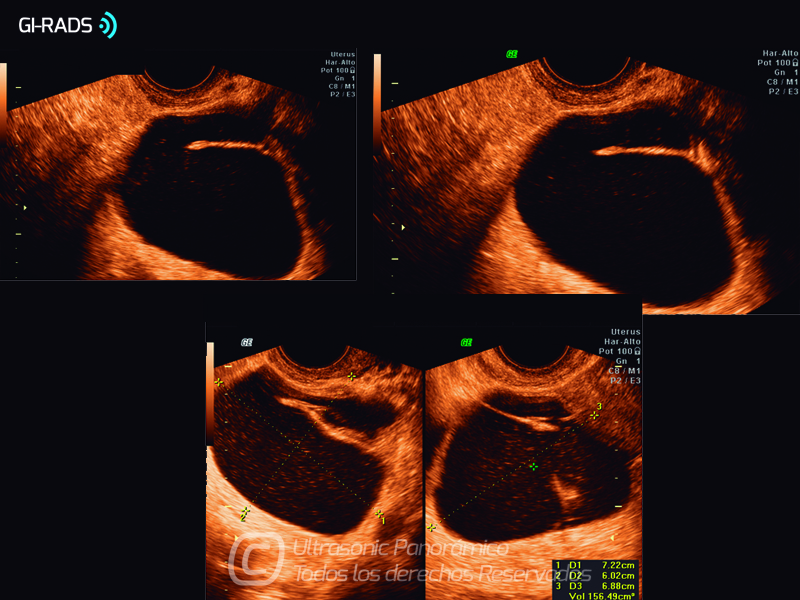

Patologías Benignas – Hidrosalpinx